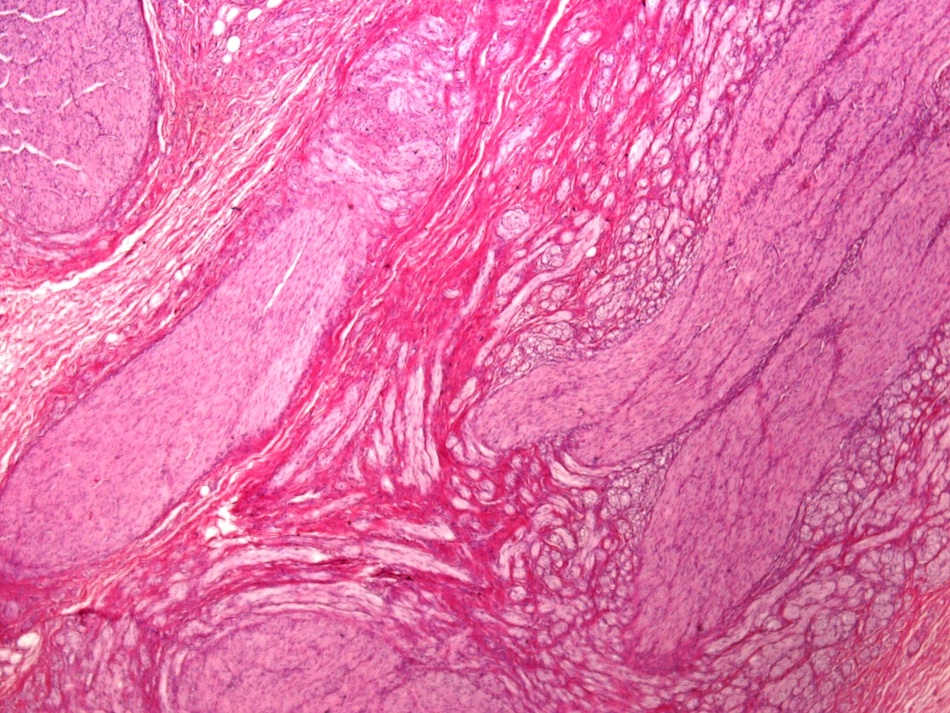

Microscopic images:

Microscopic images:

Both cases showed disorganized and thickened nerve bundles composed of spindle shaped cells, without atypia. Case A also showed a focal foreign body type giant cell reaction adjacent to the disorganized nerve bundles and a strongly immunoreactive S100 stain.

Histology typically shows hyperplastic nerve bundles, positive for S100.

Both cases showed disorganized and thickened nerve bundles composed of spindle shaped cells, without atypia. Case A also showed a focal foreign body type giant cell reaction adjacent to the disorganized nerve bundles and a strongly immunoreactive S100 stain.

Histology typically shows hyperplastic nerve bundles, positive for S100.